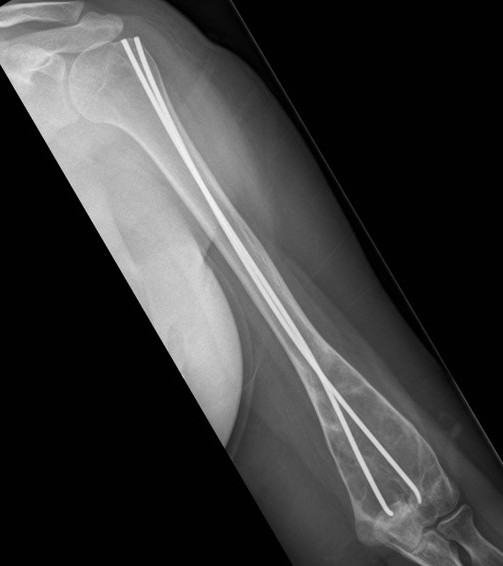

Corrective osteotomy / Intra-medullary nailing

Mainstay of treatment

Ippolito et al J Orthop Traumatol 2023

- 24 patients with 34 femurs and 14 tibias requiring intra-medullary nailing

- mean age 32

- osteotomy and deformity correction often required

- nonunion / delayed union / implant failure in 5 cases